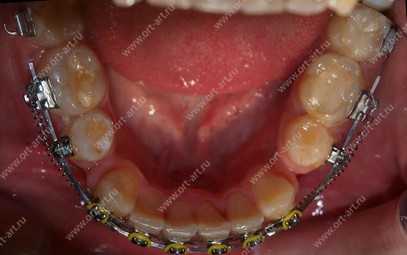

Установка брекетов

Во время основного этапа коррекции неправильного прикуса производят установку брекетов, для их фиксации используются клеевые композиты. Однако, в зависимости от типа брекетов используются разные методики установки. Каждый вестибулярный брекет наклеивают на переднюю поверхность зубов, которые нуждаются в коррекции, далее на них крепят опорные кольца, а в замочки продевают силовую дугу. Дуга изготавливается из материалов, обладающих эластичностью и упругостью, за счет чего она стремиться занять ту форму, которую ей придали первоначально.

Лингвальные брекеты установить сложнее, так как внутренний рельеф зубного ряда разнообразнее. Вначале делается слепок зубных рядов, после чего брекет-система отрабатывается на данной конструкции и только потом фиксируется клеем на внутренней поверхности зубов.